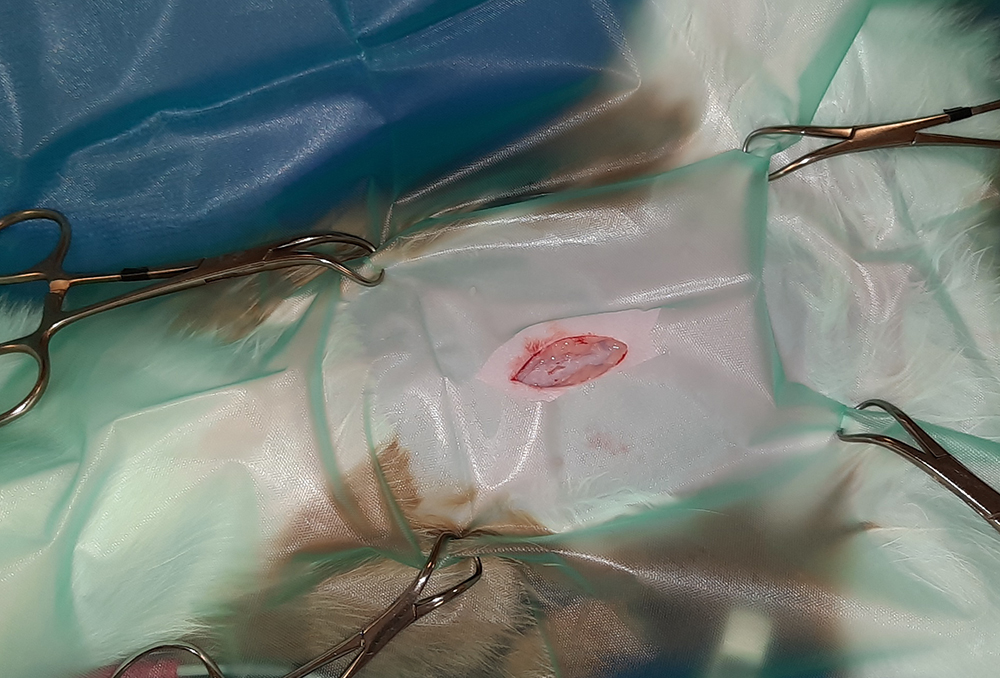

Er wordt een kleine snede gemaakt in de buik, ter hoogte van de navel. Vervolgens worden na elkaar de twee ovaria (=eierstokken) opgezocht, de aanvoerende bloedvaten afgebonden en de eierstokken verwijderd. Hierna wordt de buik in 3 lagen gesloten; de spierlaag, de onderhuid en de huid. Deze laatste wordt onderhuids gesloten met soms een enkele uitwendige knoophechting, zodat er zo min mogelijk hechtingen zichtbaar zijn. Er wordt een wondpleister geplaatst, nadat het wondgebied voorzichtig is schoongemaakt.